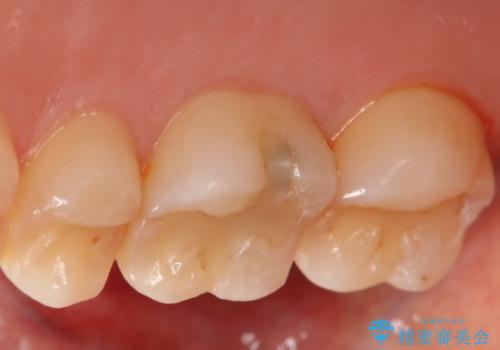

- 右上6番の虫歯治療を主訴に来院された患者様です。

切削量・形態を考慮し、セラミックインレーでの治療を計画しました。

保険の材料が劣化し中で虫歯が進行していたので、全て取り除いた上で形を整え型をとりインレーをセットしています。